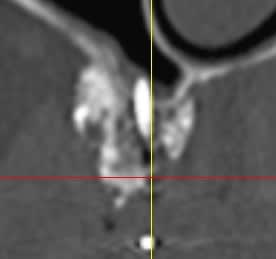

D'aprés ce que je vois, il semblerait qu'il n'y ait pas eu de greffe d'apposition à proprement parlé, mais utilisation d'une portion de corticale en occlusal pour maintenir le bio-oss.

Si ce que je vois à gauche est une vis, elle s'est mobilisée et tout le reste avec.

Il semblerait qu'il y ait eu , de plus, colonisation de la greffe d'une part via la vis qui transperce le sinus, et d'autres part part la dent adjacente ( image radio claire autour de cette dent).

Personnellement je pense que la greffe n'a pas fonctionnée et que ton confrère va se retrouver dans une bouillie inutilisable.